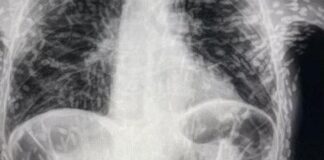

Tenya'ların bu kadar saldırgan olduğunu kim tahmin ederdi! Organları deldi geçti, beyne yumurtalarını bıraktı!

Brezilyalı doktorlar, kendilerini şaşırtan bir vakanın röntgen görüntülerini paylaştı. İyileşmeyen öksürük...